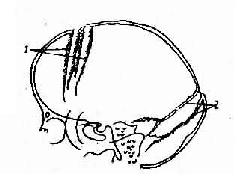

颅骨为一坚硬外壳,容量有限。某些颅内疾病,例如脑瘤脑积水,使颅内容物增多,则压力增高,进而引起一系列颅骨的改变。一般持续3~6个月即可出现X线变化,主要表现如下(图2-22、23):

颅内高压所致蝶鞍改变

图2-22 颅内高压所致蝶鞍改变

1.蝶鞍改变是成年患者颅内压增加的重要表现。早期改变为后床突鞍背骨质吸收,密度减低和轮廓模糊。进一步发展可见鞍底因骨质吸收而密度减低和轮廓模糊。鞍内病变可使蝶鞍增大,前后径及深径都增加,与颅内压增加引起的蝶鞍改变不同。